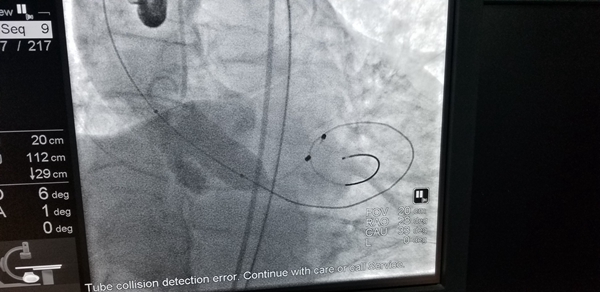

74岁的陶某是一名重度主动脉瓣狭窄的患者,曾多次因心绞痛及心力衰竭住院,生活质量极差,并且症状逐渐加重,传统药物治疗无法明显改善患者的病情。经胸心外科医生会诊后建议开胸行主动脉瓣置换术。但开胸手术痛苦大,风险高,术后并发症多,这让病人及家属十分担忧。此后陶某听闻我院心内科严金川主任对心脏的介入治疗有着丰富的经验以及高超的技术,于是前来就医询问是否可以通过微创介入手术换瓣。严主任仔细询问患者病史并做了详细的相关检查,确定该患者符合经导管主动脉置换术(TAVI)的适应症,并且无微创介入手术禁忌症。医院领导高度重视该项新技术的开展,多次组织心血管内科、心外科、麻醉科、影像科、心脏超声、医务及护理等多学科多部门反复讨论,最后经医学伦理委员会专家投票一致通过了该项新技术的临床实施。手术方案决定采用经股动脉微创介入方式。由于手术操作复杂,需要多专科团队人员的协作,技术难度高,严主任领衔的心脏介入团队为此进行了缜密准备,制定了详细的风险应急预案,多学科密切配合,最大程度地保障患者的安全。TAVI术中通过股动脉送入介入导管,首先采用扩张球囊对患者重度钙化狭窄的主动脉瓣膜进行预扩张,后将人工主动脉瓣膜送到拟释放位置,经反复造影精确定位,瓣膜位置合适,人工瓣膜顺利释放,替换了原来重度钙化、狭窄的瓣膜,术中经食道超声确认新的瓣膜位置准确、开放自如,无瓣膜返流,患者主动脉瓣的功能得以恢复,手术成功。术后1个小时,患者就已经清醒,目前生命体征平稳,恢复良好,胸闷气喘症状显著改善,现在已可以自由下床活动。